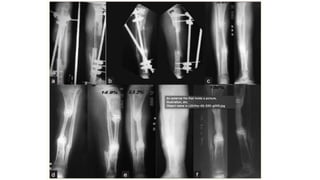

Huntingtons procedure • Transpositionof the ipsilateral fibula to the tibia • Provides mechanical strength. • the fibula is transferred to the tibia as a pedicle graft. • Due to retained blood supply to one end of the transplant, the graft easily takes up and hypertrophies upon weightbearing over a period of time

Ilizarov method • Lawof tension stress and distraction osteogenesis • Corticotomy is done in the fracture fragments and both the fragments are distracted. • When the desired length is achieved, distraction is stopped and consolidation of the new bone formed occurs • Gold standard in infective gap non union • Fibular osteotomy

• 21.

• Removal offixator: Atleast three cortices should be ossified in AP and Lat view xrays Protected weight bearing • Advantages: no skin incision is made, minimally invasive (wires and pins) Very little soft tissue handling Can correct length and deformities in three dimensions Patient can weight bear early after application